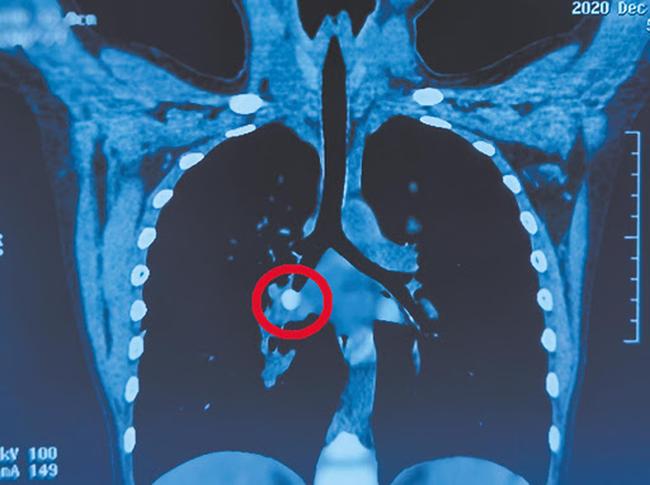

Hình ảnh chiếc răng mắc kẹt trong phế quản

Tiếp đó, các bác sĩ tiến hành chụp CT phổi cho cậu bé thì phát hiện có dị vật ở vùng dưới phổi phải, làm tắc phế quản. Theo nhận định của bác sĩ, vì Gia Gia còn nhỏ nên khả năng hồi phục nhanh nhưng bác sĩ vẫn quyết định nội soi để lấy dị vật.

Sau 90 phút, ca mổ kết thúc, dị vật được lấy ra ngoài chính là chiếc răng bị lung lay của Gia Gia. Tuy nhiên, do mắc kẹt quá lâu, cái răng đã làm phổi của Gia Gia sưng to, có hạt viêm và mủ. Các bác sĩ ngay sau đó phải tiến hành rửa phế nang cho Gia Gia.